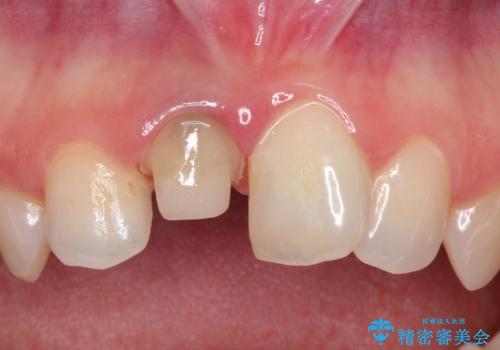

前歯の治療。再根管治療~セラミッククラウン

- 前歯の痛みを主訴に来院された患者様です。

再根管治療を行い、セラミックにて被せものを行いました。

症状も改善され満足して頂きました。